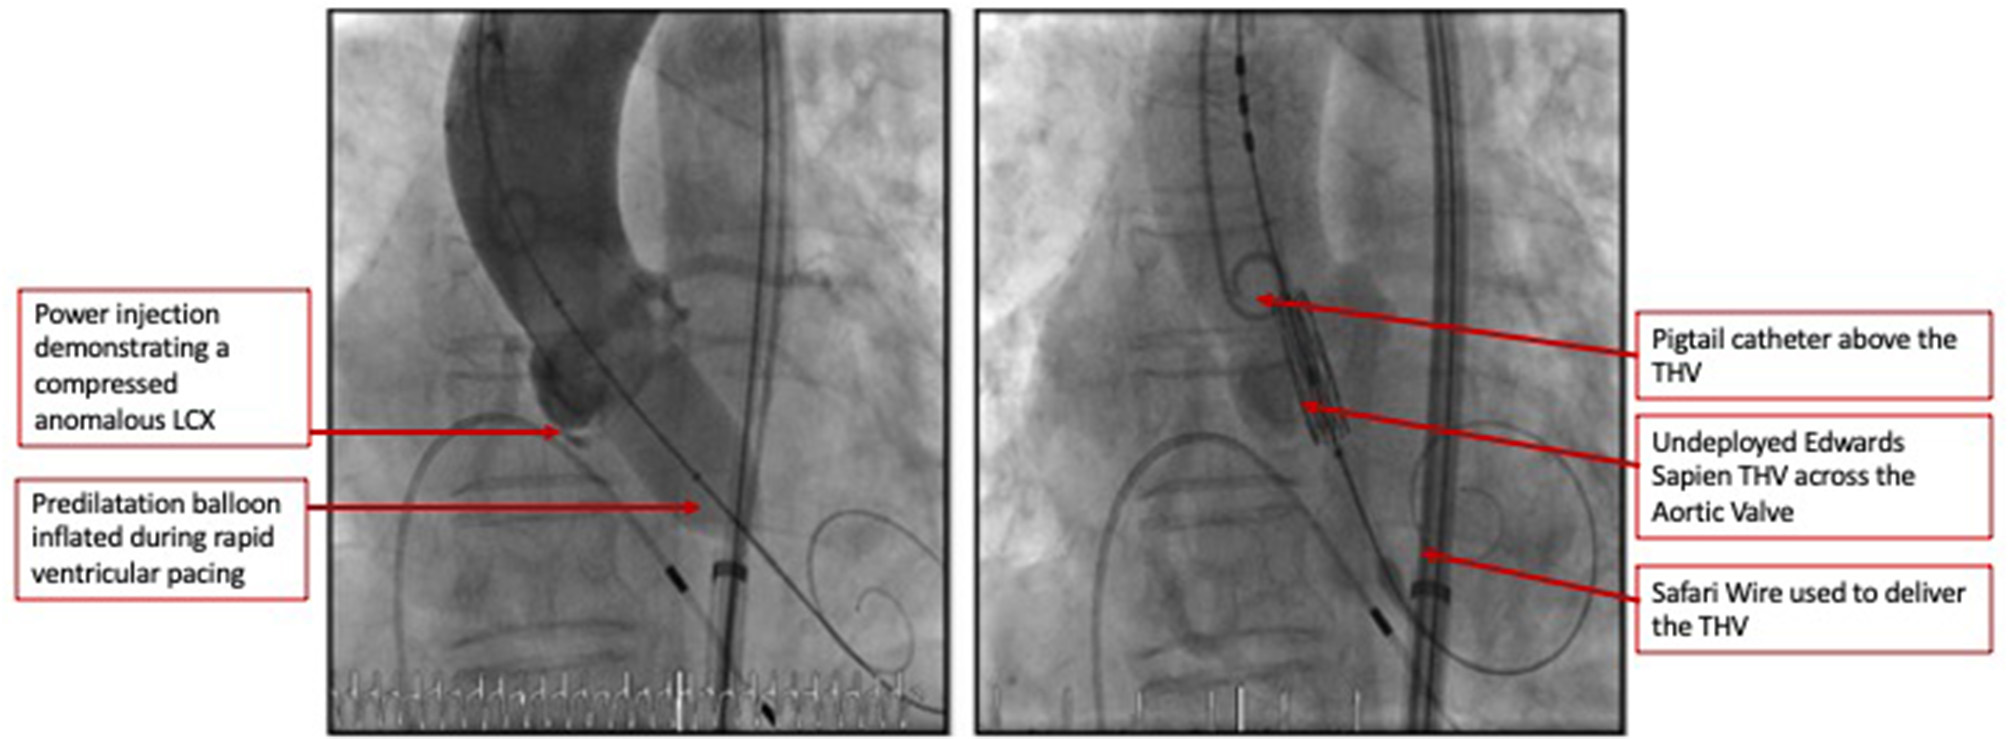

The heart team-meeting consensus was to proceed with TAVR using an Edwards SAPIEN valve with high implant. Alternate access should be obtained to rescue the anomalous LCX. The patient underwent the procedure successfully as follows: Through the left common femoral vein sheath, a temporary pacing wire was inserted. Through the left arterial sheath, a pigtail was advanced. Through the right arterial sheath, an Edwards SAPIEN delivery sheath was advanced over a Sapphire wire that had been placed in the LV through the standard method. The valve was predilated using rapid pacing, and an angiogram through the pigtail catheter demonstrated a patent RCA, LCX, and LM artery ostial with some compression of the LCX midsegment. As such, the decision was to proceed as planned with a high implant of the Edwards SAPIEN valve (Figure 2). The implant was performed with rapid ventricular pacing. Angiography using a power injector confirmed appropriate expansion of the valve and no paravalvular regurgitation. Selective angiography of the LCX with a 6-French AL 0.75 guiding catheter confirmed widely patent coronary arteries (Figure 3). The echocardiogram further confirmed the angiographic findings. Post procedure, the gradient by echocardiography was 7 mmHg, and the EF had improved to 44.5% (Supplementary Figure 2). The improvement in EF could be due to inter-observer variability although it is uncommon to be this wide of a range. It may indicate timely replacement with improvement in the left ventricular systolic and diastolic functions. Imaging including cardiac MRI could identify fibrosis that may suggest poor recovery. This was not performed in this patient. The postoperative course was uneventful, and she was discharged on day 3 in stable condition without a need for a pacemaker on dual antiplatelet therapy (aspirin 81 mg and clopidogrel 75 mg daily). She was evaluated after 1 month at an outpatient clinic, where she was completely asymptomatic. A repeat CCT demonstrated thin leaflets with normal mobility and a widely patent LCX (Figure 4 and Supplementary Figure 3).

Figure 2

Coronary angiogram demonstrated a patent RCA and LM artery ostia with some compression of the LCX's mid segment. As such the decision was to proceed as planned with a high implant of the Edwards Sapien 3 valve.